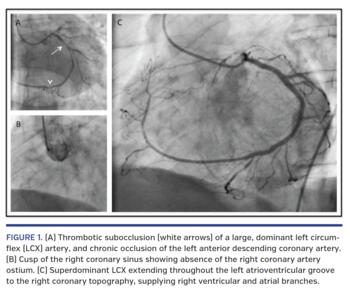

Coronary angiography showed a large, dominant left circumflex (LCX) artery with subocclusive thrombus burden (Figure 1A). The left anterior descending (LAD) artery was chronically occluded in the proximal segment, and the right coronary artery ostium was absent despite several attempts to locate it at the right coronary sinus and at different sites of possible anatomic variations (Figure 1B). Primary percutaneous coronary intervention (PCI) was successfully performed in the proximal and mid segments of the LCX with two drug-eluting stents. After restoration of normal flow, angiography clarified a superdominant LCX with extended course through the left atrioventricular groove and right coronary topography, supplying the right ventricular and atrial branches (Figure 1C). Intracoronary collaterals to the distal LAD were noted arising from the distal LCX. The patient recovered well after the procedure without major complications, but developed severe left ventricular dysfunction with an ejection fraction of 26% by transthoracic echocardiogram.